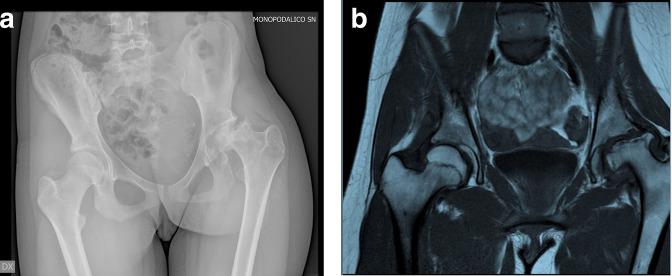

Avascular femoral head necrosis in the context of gymnastics is a rare but serious complication, appearing similar to Perthes' disease but occurring later during adolescence. Based on 3D CT animations, we propose repetitive impact between the main supplying vessels on the posterolateral femoral neck and the posterior acetabular wall in hyperextension and external rotation as a possible cause of direct vascular damage, and subsequent femoral head necrosis in three adolescent female gymnasts we are reporting on.

在体操运动中发生的股骨头缺血性坏死是一种罕见但严重的并发症,其表现与佩吉特氏病相似,但发生在青春期后期。基于三维CT动画,我们提出在超伸展和外旋时,股骨颈后外侧主要供血血管与髋臼后壁之间的反复撞击可能是导致直接血管损伤的原因,进而导致我们报道的三名青春期女性体操运动员发生股骨头坏死。